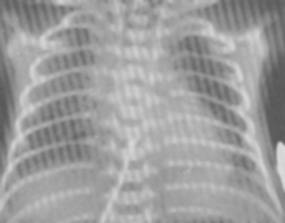

►Particularitati ale imaginii radiologice toraco-pulmonare la copil

1. Toracele:    - la sugar si copilul mic este scurt, diametrul bazal mare si coaste orizontalizate;

- pe masura dezvoltarii creste mai mult vertical si se turteste antero-posterior.

2. Inima:    - este orizontalizata datorita pozitiei inalte a diafragmului (ficat mare, aerocolie) si datorita compresiunii timusului;

- conul arterei pulmonare este proeminent, iar butonul aortei invizibil;

- in ansamblu imaginea cardio-vasculara ia aspectul configuratiei mitrale;

- imaginea cardio-vasculara asemanatoare celei a adultului se evidentiaza dupa varsta de 7 ani.

3. Diafragmul: - are pozitie inalta la sugari, proiectandu-se uneori in spatiul 3 intercostal.

4. Mediastinul: - ocupa un spatiu mai mare, are un pedicul vascular mai larg, fara imaginea butonului aortic pana la 5-6 ani.

5. Timusul:    - situat in mediastinul superior si anterior are forma triunghiulara, cu margini ondulate, se mareste in expir.

6. Plamanii: - au tesut interstitial mai bogat si mai bine vascularizat aparand mai putin aerati si mai hiperemiati (desen pulmonar mai accentuat) fata de adult;

- hilurile sunt mari, cel stang frecvent mascat de cord.